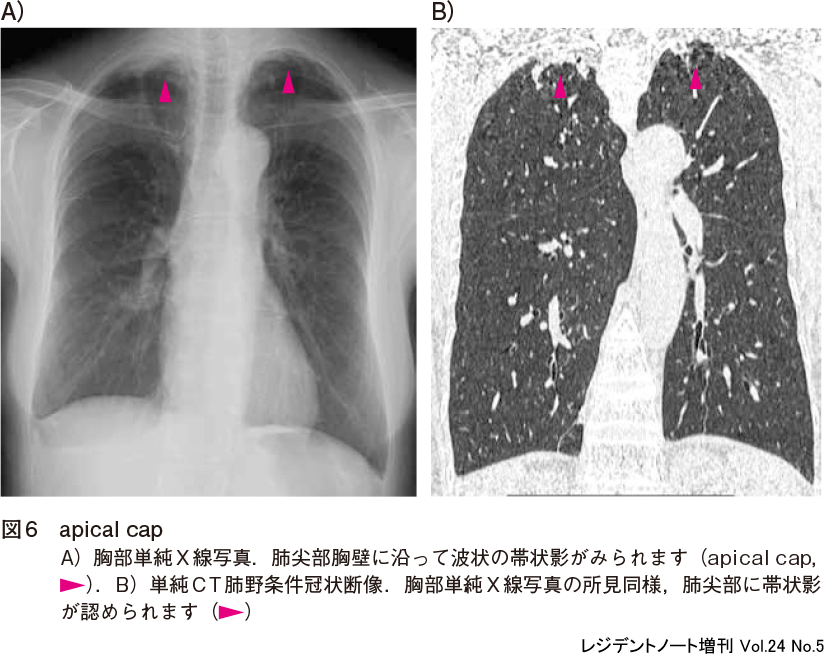

X線診断の基礎知識|胸部写真の読み方|太田東こども&おとな診療所|こどもとおとなの病気について、気軽に相談できる診療所です。, レジデントノート増刊:読影力がグッと上がる!胸部X線写真・CTの読み方、考え方〜疾患別に読影の基本と各科での経過観察のポイント、撮影のタイミングがイチからわかる! - 羊土社,

レジデントノート増刊:読影力がグッと上がる!胸部X線写真・CTの読み方、考え方〜疾患別に読影の基本と各科での経過観察のポイント、撮影のタイミングがイチからわかる! - 羊土社, Amazon.co.jp: 気管支の枝読みで考える 胸部画像診断入門 ── 肺既存構造と区域解剖学から学ぶ読影の基礎 ─ 電子版付 ─ : 佐藤 功(清仁会宇多津病院放射線科画像診断センター長): Japanese Books